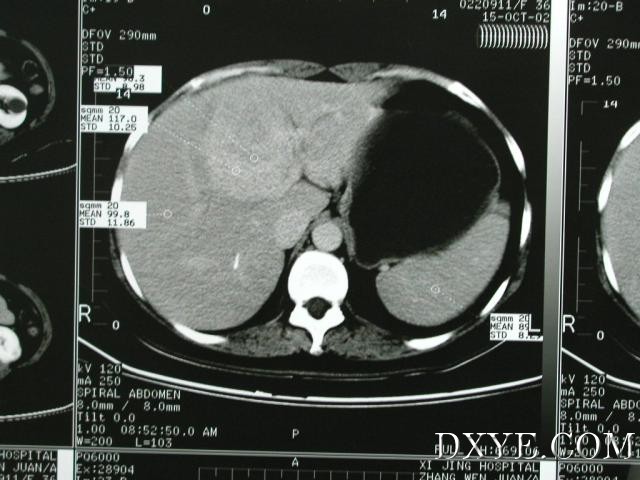

比前一张CT高一些的位置,可见肿瘤与门静脉左右支的关系。从CT片可以看出,

手术

的重点是在保证完整切除肿瘤的同时,保护门静脉左右支(尤其是门静脉右支)